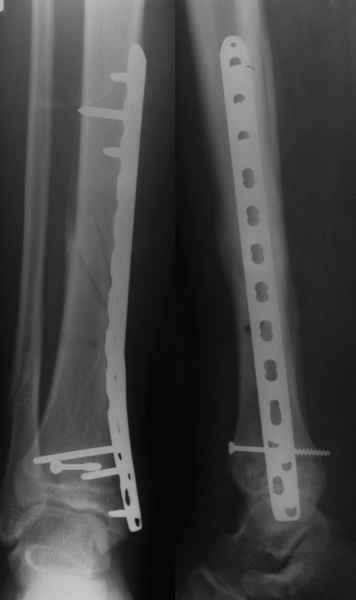

В приложении метафизарный перелом у ребёнка 14лет, с распространением линии перелома на зону роста.

В примере показан не перелом пилона, а эпифизеолиз, м/берцовую кость сознательно не фиксировал(длина её восстановлена, ротации нет),у детей стараемся минимизировать операц.травму, несколько позже разрешил полную нагрузку на ногу(4 недели). Но принцип фиксации б/берцовой кости м.б. таким же.

Уважаемые коллеги, остеосинтез малоберцовой кости при переломах пилона помогает решить, как минимум, 3 задачи:

1. шинировать сегмент. При переломах типа С, как правило, остеосинтез большеберцовой кости выполняется по спаданию отёка и заживлению мягких тканей, как и говорит об этом чуть ниже Djoldas. В этот период - с момента поступления пациента в стационар до собственно остеосинтеза перелома пилона мы можем стабилизировать конечность или путём остеосинтеза малоберцовой кости, или ExFix. Естественно, одно не равнозначно другому, для каждого метода есть свои показания в зависимости от характера перелома;

2. за счёт эффекта лигаментотаксиса восстановить правильные взаимоотношения в большеберцово-таранном сочленении. И действительно, я полностью согласен с Вами, Александр, такую же задачу мы решаем зачастую с помощью ExFix. И если наружная фиксация при переломе пилона является не методом первого этапа, а окончательным методом лечения перелома - ни о каком дополнительном остеосинтезе малоберцовой кости, как правило, речи не идёт и идти не должно. Но, если мы решили выполнить внутреннюю фиксацию, желательно помнить, что остеосинтез малоберцовой кости при переломе пилона помогает решить и ещё одну задачу - ортопедическую:

3. стабилизировать наружный опорный комплекс голени и предотвратить вальгусную деформацию голеностопного сустава. Конечно, данная проблема не очень актуальна, или вовсе не актуальна для 43С1, но для повреждений типа 43С2,3, особенно в случаях, когда метафизарный дефект потребовал пластики, а пластину пришлось уложить по медиальной стороне - остеосинтез малоберцовой кости является крайне необходимым - привожу характерный пример.

Но перелом малоберцовой кости может быть и много проксимальнее, и его так же приходится фиксировать из этих же соображений. И особенно, если пациент полный. Из отечественных хирургов на возможность развития такого осложнения - вальгусной деформации голеностопного сустава ч/з 2-3 месяца после операции при переломах типа 43С2 в отсутствии фиксации малоберцовой кости одним из первых указал Виталий Дрягин из ГКБ №3 Челябинска ещё в конце 90х.